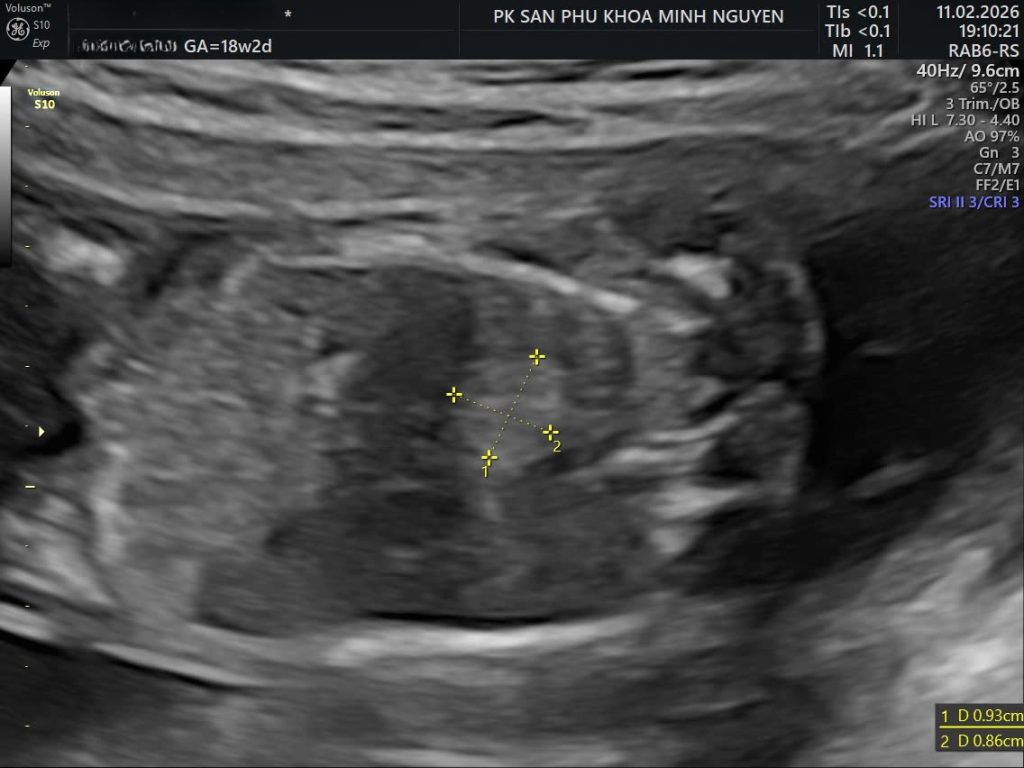

Trên siêu âm thai, bệnh nang tuyến phổi có thể biểu hiện bằng một nang lớn, nhiều nang nhỏ hoặc một khối tăng âm đồng nhất trong lồng ngực.

Bác sĩ sẽ đánh giá vị trí khối, kích thước, mức độ đẩy lệch trung thất và ảnh hưởng đến tim thai. Một yếu tố quan trọng là có hay không dấu hiệu phù thai.

Type 1 có một hoặc vài nang lớn, thường trên 2 cm.

Theo dõi định kỳ mỗi 2 đến 4 tuần giúp đánh giá xu hướng tăng hay giảm kích thước khối. Nhiều trường hợp có xu hướng ổn định hoặc giảm kích thước ở quý ba.

Nếu tổn thương CPAM có kích thước lớn, đẩy lệch trung thất hoặc làm tim bị chèn ép, MRI giúp đánh giá chính xác hơn thể tích khối và mức độ ảnh hưởng đến phổi lành.

Trong trường hợp hình ảnh siêu âm bị hạn chế do tư thế thai hoặc điều kiện khảo sát, MRI có thể cung cấp thêm thông tin giải phẫu chi tiết.